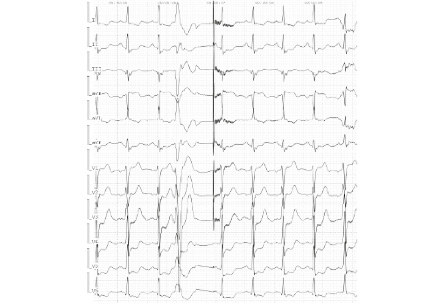

Электрокардиография (ЭКГ). Артифициальный ритм со стимуляцией предсердий, частота сердечных сокращений (ЧСС) 55 уд/мин. Нарушение внутрижелудочкового проведения. Признаки рубцового поражения миокарда нижней локализации (рис. 1).

Рис. 1. ЭКГ пациента при поступлении.

На 1-е сутки после ТИАК пациент предъявил жалобы на боли в левой половине грудной клетки и незначительную одышку в горизонтальном положении, которые купировались самостоятельно при смене положения тела. На ЭКГ синусовый ритм с ЧСС 95 уд/мин, умеренно выраженная депрессия сегмента ST в отведениях V4–6 с переходом в слабоотрицательный зубец Т при нормальной амплитуде зубца R во всех отведениях (рис. 7). Динамика ЭКГ интерпретирована дежурным врачом как тахизависимые изменения реполяризации (ЧСС 95 уд/мин) на фоне хронической окклюзии правой коронарной артерии. Назначен анаприлин в дозе 40 мг в сочетании с одной дозой нитроглицерина. После изменения положения тела болевой синдром купировался в течение нескольких минут. При контрольной ЭКГ через 3 ч отмечалось уменьшение депрессии сегмента ST в V4–6 на фоне урежения ЧСС до 76 уд/мин (рис. 8). Жалоб пациент не предъявлял. Учитывая атипичный характер болевого синдрома, он был расценен как позиционная вертеброгенная дорсопатия у пациента с выраженным кифосколиозом.

Рис. 7. ЭКГ на 1-е сутки после перевода из отделения реанимации.

На 3-и сутки после операции во время прогулки по коридору произошло резкое ухудшение состояния в виде приступа удушья, учащенного сердцебиения, выраженной слабости. Объективно: бледность кожных покровов, холодный пот, тахипноэ до 25 в минуту, множественные мелкопузырчатые хрипы надо всей поверхностью легких, глухость сердечных тонов, ЧСС 95 уд/мин, артериальное давление 140/80 мм рт. ст. На ЭКГ депрессия сегмента ST до 3 мм в V3–6, элевация сегмента ST в aVR (рис. 9).

Рис. 9. ЭКГ в момент резкого ухудшения состояния.